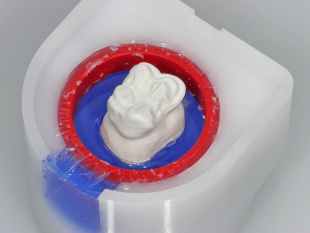

210 Jet Cube, большая 27 776 руб.- + В корзину

215 Jet Cube, малая 30 482 руб.- + В корзину - Вы можете задать любой интересующий вас вопрос по товару или работе магазина. Наши квалифицированные специалисты обязательно вам помогут.